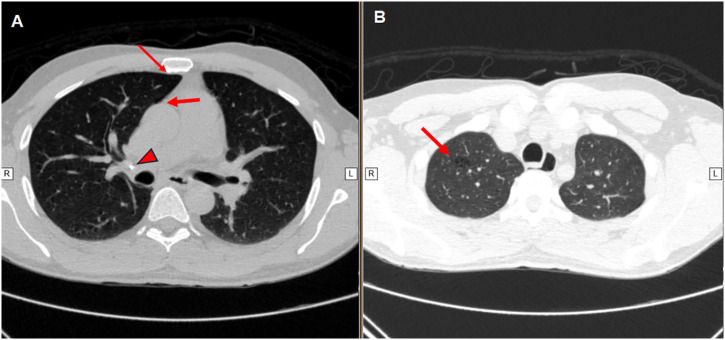

Urogenital tuberculosis (UGT) constitutes a significant extrapulmonary form of tuberculosis, often presenting non-specific symptoms and a prolonged indolent course that leads to delayed diagnosis and treatment, which can result in severe and irreversible complications such as urinary strictures, renal failure, and infertility. This report describes a case of a 38-year-old man with a five-month history of low back pain, hematuria, dysuria, and altered urinary frequency. Initial treatment for a presumed urinary tract infection failed, and subsequent diagnostic investigations showed stones, nodules, and cysts in his left kidney. A positive tuberculin skin test confirmed the diagnosis of UGT and identification of Mycobacterium tuberculosis in urine samples. The patient underwent standard six-month antituberculosis therapy and subsequent retreatment due to persistent symptoms. Despite significant symptom amelioration, irreversible urological sequelae, including infundibular stenosis, polyuria, and nocturia, remained. This case underscores the importance of early suspicion, accurate diagnosis, and timely treatment of UGT to minimize long-term complications. It also highlights the potential need for extended treatment length in complex cases to improve outcomes and reduce sequelae, warranting further research in this area.